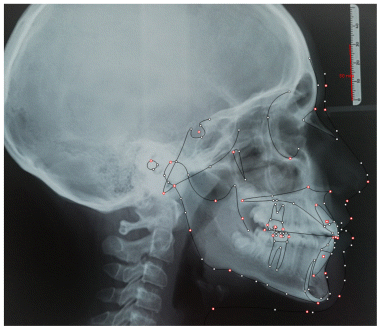

Case 4

The patient presented in early mixed dentition with a complete anterior crossbite associated with a bilateral posterior crossbite, resulting in a functional mandibular shift and lower dental midline deviation (Figures 27–34) (Table 7). Extraoral examination revealed a flat facial profile with a tendency toward convexity, a long facial pattern, and mild facial asymmetry, consistent with a functional component superimposed on an underlying skeletal Class III tendency. The treatment protocol involved the use of an AMCOP TC appliance, designed to address the transverse maxillary deficiency and eliminate the functional shift. The appliance allowed progressive transverse development of the maxillary arch, promoting spontaneous mandibular repositioning and restoration of a more physiologic maxillomandibular relationship during growth. Following active treatment, a complete correction of both anterior and posterior crossbite was achieved. Transverse arch coordination was obtained, with elimination of the unilateral posterior crossbite and resolution of the functional mandibular deviation. The occlusion was stabilized in a dental Class I relationship, with normalization of overjet and overbite and centering of the lower dental midline relative to the maxillary midline. From a sagittal perspective, the correction of the functional shift contributed to an improvement in the intermaxillary relationship, with favorable dentoalveolar adaptation and reduction of compensatory incisor inclinations. Vertical relationships remained stable throughout treatment, maintaining a normodivergent growth pattern. Extraoral assessment after treatment showed an improvement in facial balance and symmetry, with a more harmonious sagittal profile compared to baseline. The correction of occlusal relationships allowed a more stable mandibular posture, positively influencing soft tissue profile and facial proportions. The post-treatment lateral cephalogram (Table 8) and the clinical, occlusal, and photographic records clearly demonstrate total correction of the malocclusion, supporting the effectiveness of early interceptive treatment with AMCOP TC in patients with Class III malocclusion associated with transverse maxillary deficiency and functional mandibular displacement. Early orthopedic–orthodontic intervention appears to play a key role in restoring functional occlusion and guiding craniofacial development toward a more favorable pattern.

| Cephalometric Analysis after Treatment | Values (°) | Normal Values (°) |

|---|---|---|

| SNA | 79° | 82 ± 3 |

| SNB | 78,5° | 80 ± 3 |

| ANB | 0,5° | 2 ± 2 |

| OVJ | 2,5 | 3.5 ± 2,5 |

| OVB | 1,5 | 2 ± 2,5 |

| CoGoMe | 131° | 128,8 ± 4 |

| Is^Ans-Pns | 112° | 110 ± 6 |

| Li^GoGn | 100° | 94 ± 7 |

| Apg-Li | 2,0 mm | 2 ± 2 |

| Parameter | Values | Normal Values |

| SNA (°) | 80.0° | 82 ± 3 |

| SNB (°) | 79.9° | 80 ± 3 |

| ANB (°) | 0.0° | 2 ± 2 |

| Overjet (OVJ) | −5.4 mm (Wits) | 3.5 ± 2.5 |

| Overbite (OVB) | Deep bite | 2 ± 2.5 |

| CoGoMe (°) | ~132–133°* | 128.8 ± 4 |

| Upper incisor inclination (Is^Ans–Pns) | 109.4° | 110 ± 6 |

| Lower incisor inclination (Li^GoGn) | 95.1° | 94 ± 7 |

| Lower incisor compensation (Apg–Li) | ~1.5 mm | 2 ± 2 |